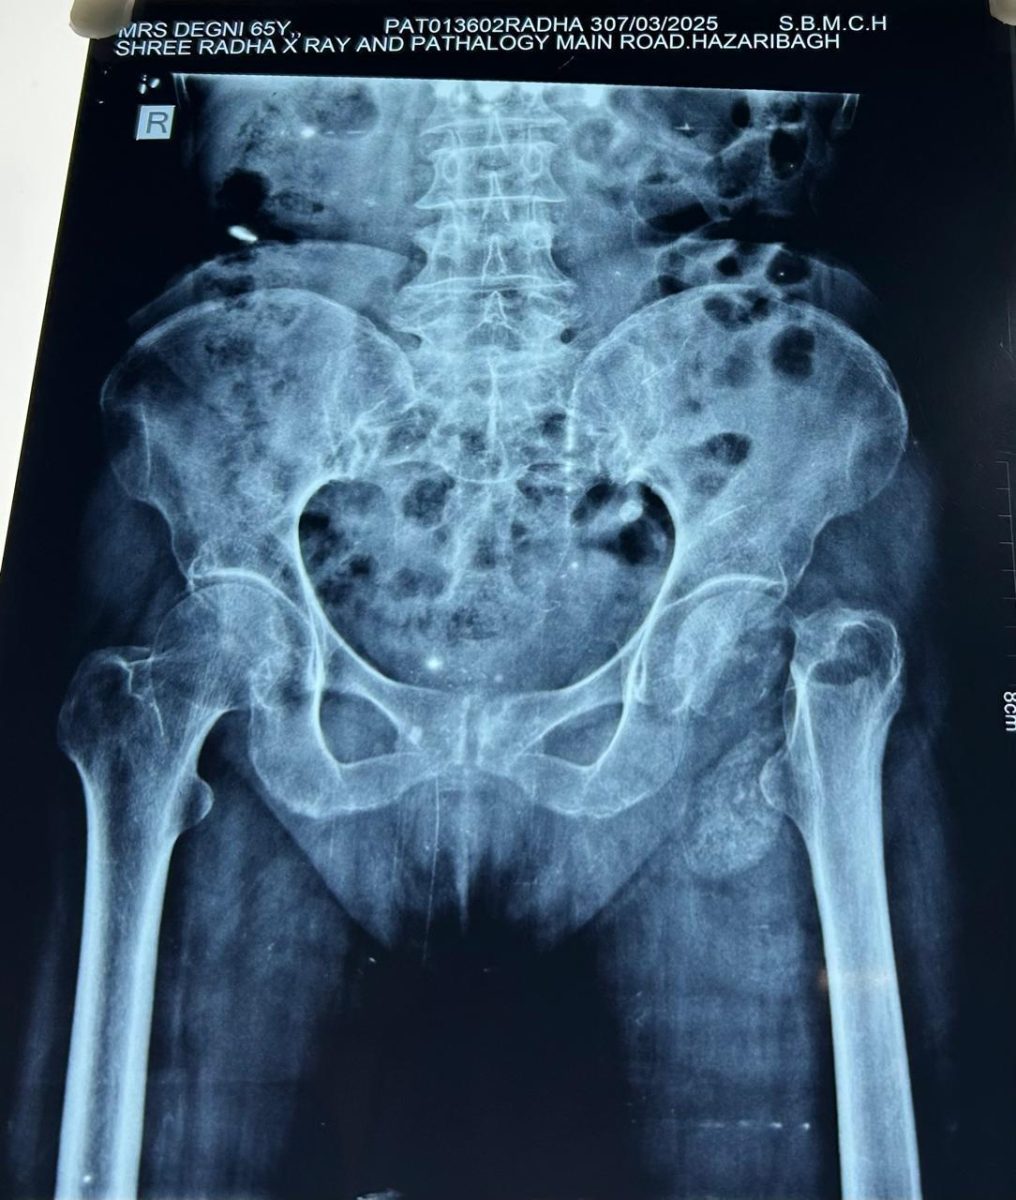

April 26, 2025Introduction A 67-year-old patient, who had been struggling with the effects of an old fracture in the neck of the femur, recently underwent a Total Hip Replacement (THR) surgery. The procedure was performed successfully, and the patient’s recovery has been remarkable, with mobility restored sooner than expected.

Patient’s Journey Before Surgery The patient had sustained a femoral neck fracture years ago, which led to persistent pain, limited mobility, and difficulty performing daily activities. Over time, the condition worsened, affecting the patient’s quality of life. After careful evaluation by the orthopedic team, it was decided that Total Hip Replacement surgery was the best course of action.

The Surgery: A Smooth and Uneventful Procedure The THR surgery was conducted under expert supervision, ensuring a smooth and complication-free experience. The orthopedic team used advanced surgical techniques to replace the damaged femoral head and acetabulum with a prosthetic implant, restoring joint function and stability.